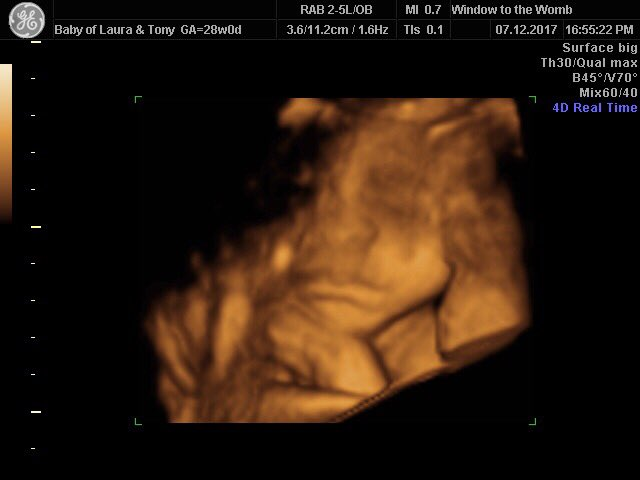

We just had to invite her in for a scan! Laura came to our Leeds clinic for a 4D + Well-being package (VIB) and had a magical time meeting baby. She got to meet baby in their protected world in stunning 4D, check on baby’s well-being with a report to take home, as well as a full scan movie, 99.9% accurate gender confirmation, photo prints, keyrings and all images on our free app and can we just say…what a gorgeous bouncing baby boy she has! He’s a little bit shy!

We’d like to wish Laura all the best in the rest of her pregnancy and thank her for visiting. Doesn’t baby look adorable? Very cosy!